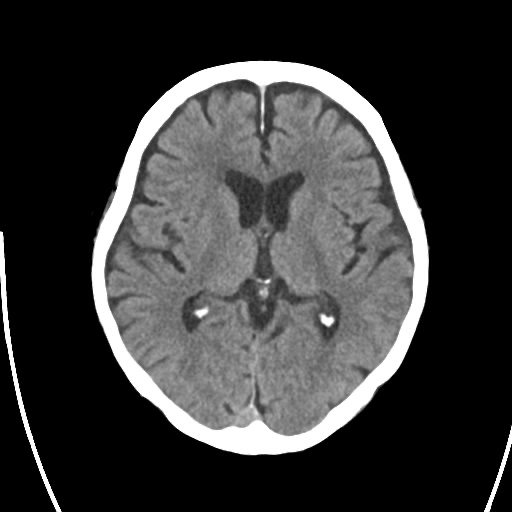

CT

当院が導入しているシーメンス社製の64列CT「SOMATOM go.Top」は、※逐次近似法の技術を搭載しており、短時間で精細な画像を提供します。この装置は、特に頭部の撮影においてその真価を発揮します。脳神経外科専門病院である当院において、頭部外傷、脳出血、くも膜下出血、骨折などの緊急を要する疾患の診断には不可欠な存在です。迅速な撮影により、病態を正確に把握し、一刻を争う治療へと繋げています。

被ばく線量に対しても最大限配慮しており、被ばく低減技術を搭載しています。患者さんのご負担を最小限に抑えつつ、質の高い画像診断を提供しています。

またAI技術を活用し誰でも同じように高いレベルで実行できるワークフローの自動化(AIワークフロー)により装置付属のタブレット端末を用いて検査室内の被検者のそばで行うことができオペレーターが被検者に寄り添うことで,被検者の不安を和らげ安心感を与えるとともに,オペレーターにとっても快適で効率的な検査を行います。